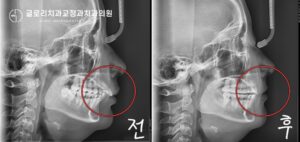

돌출 개선과 함께 임플란트 식립 공간 확보하기! 신내동 교정치과

『신내동 교정치과 김정은 원장입니다!』 오늘 여러분들께 소개해 드릴 의학정보는 돌출 개선과 함께 임플란트 식립 공간에 관한 내용 입니다. ​ 단순히 치열 개선이라 하면 삐뚤어진 곳을 올곧게 배열하는 것이라 생각하는 분들이…